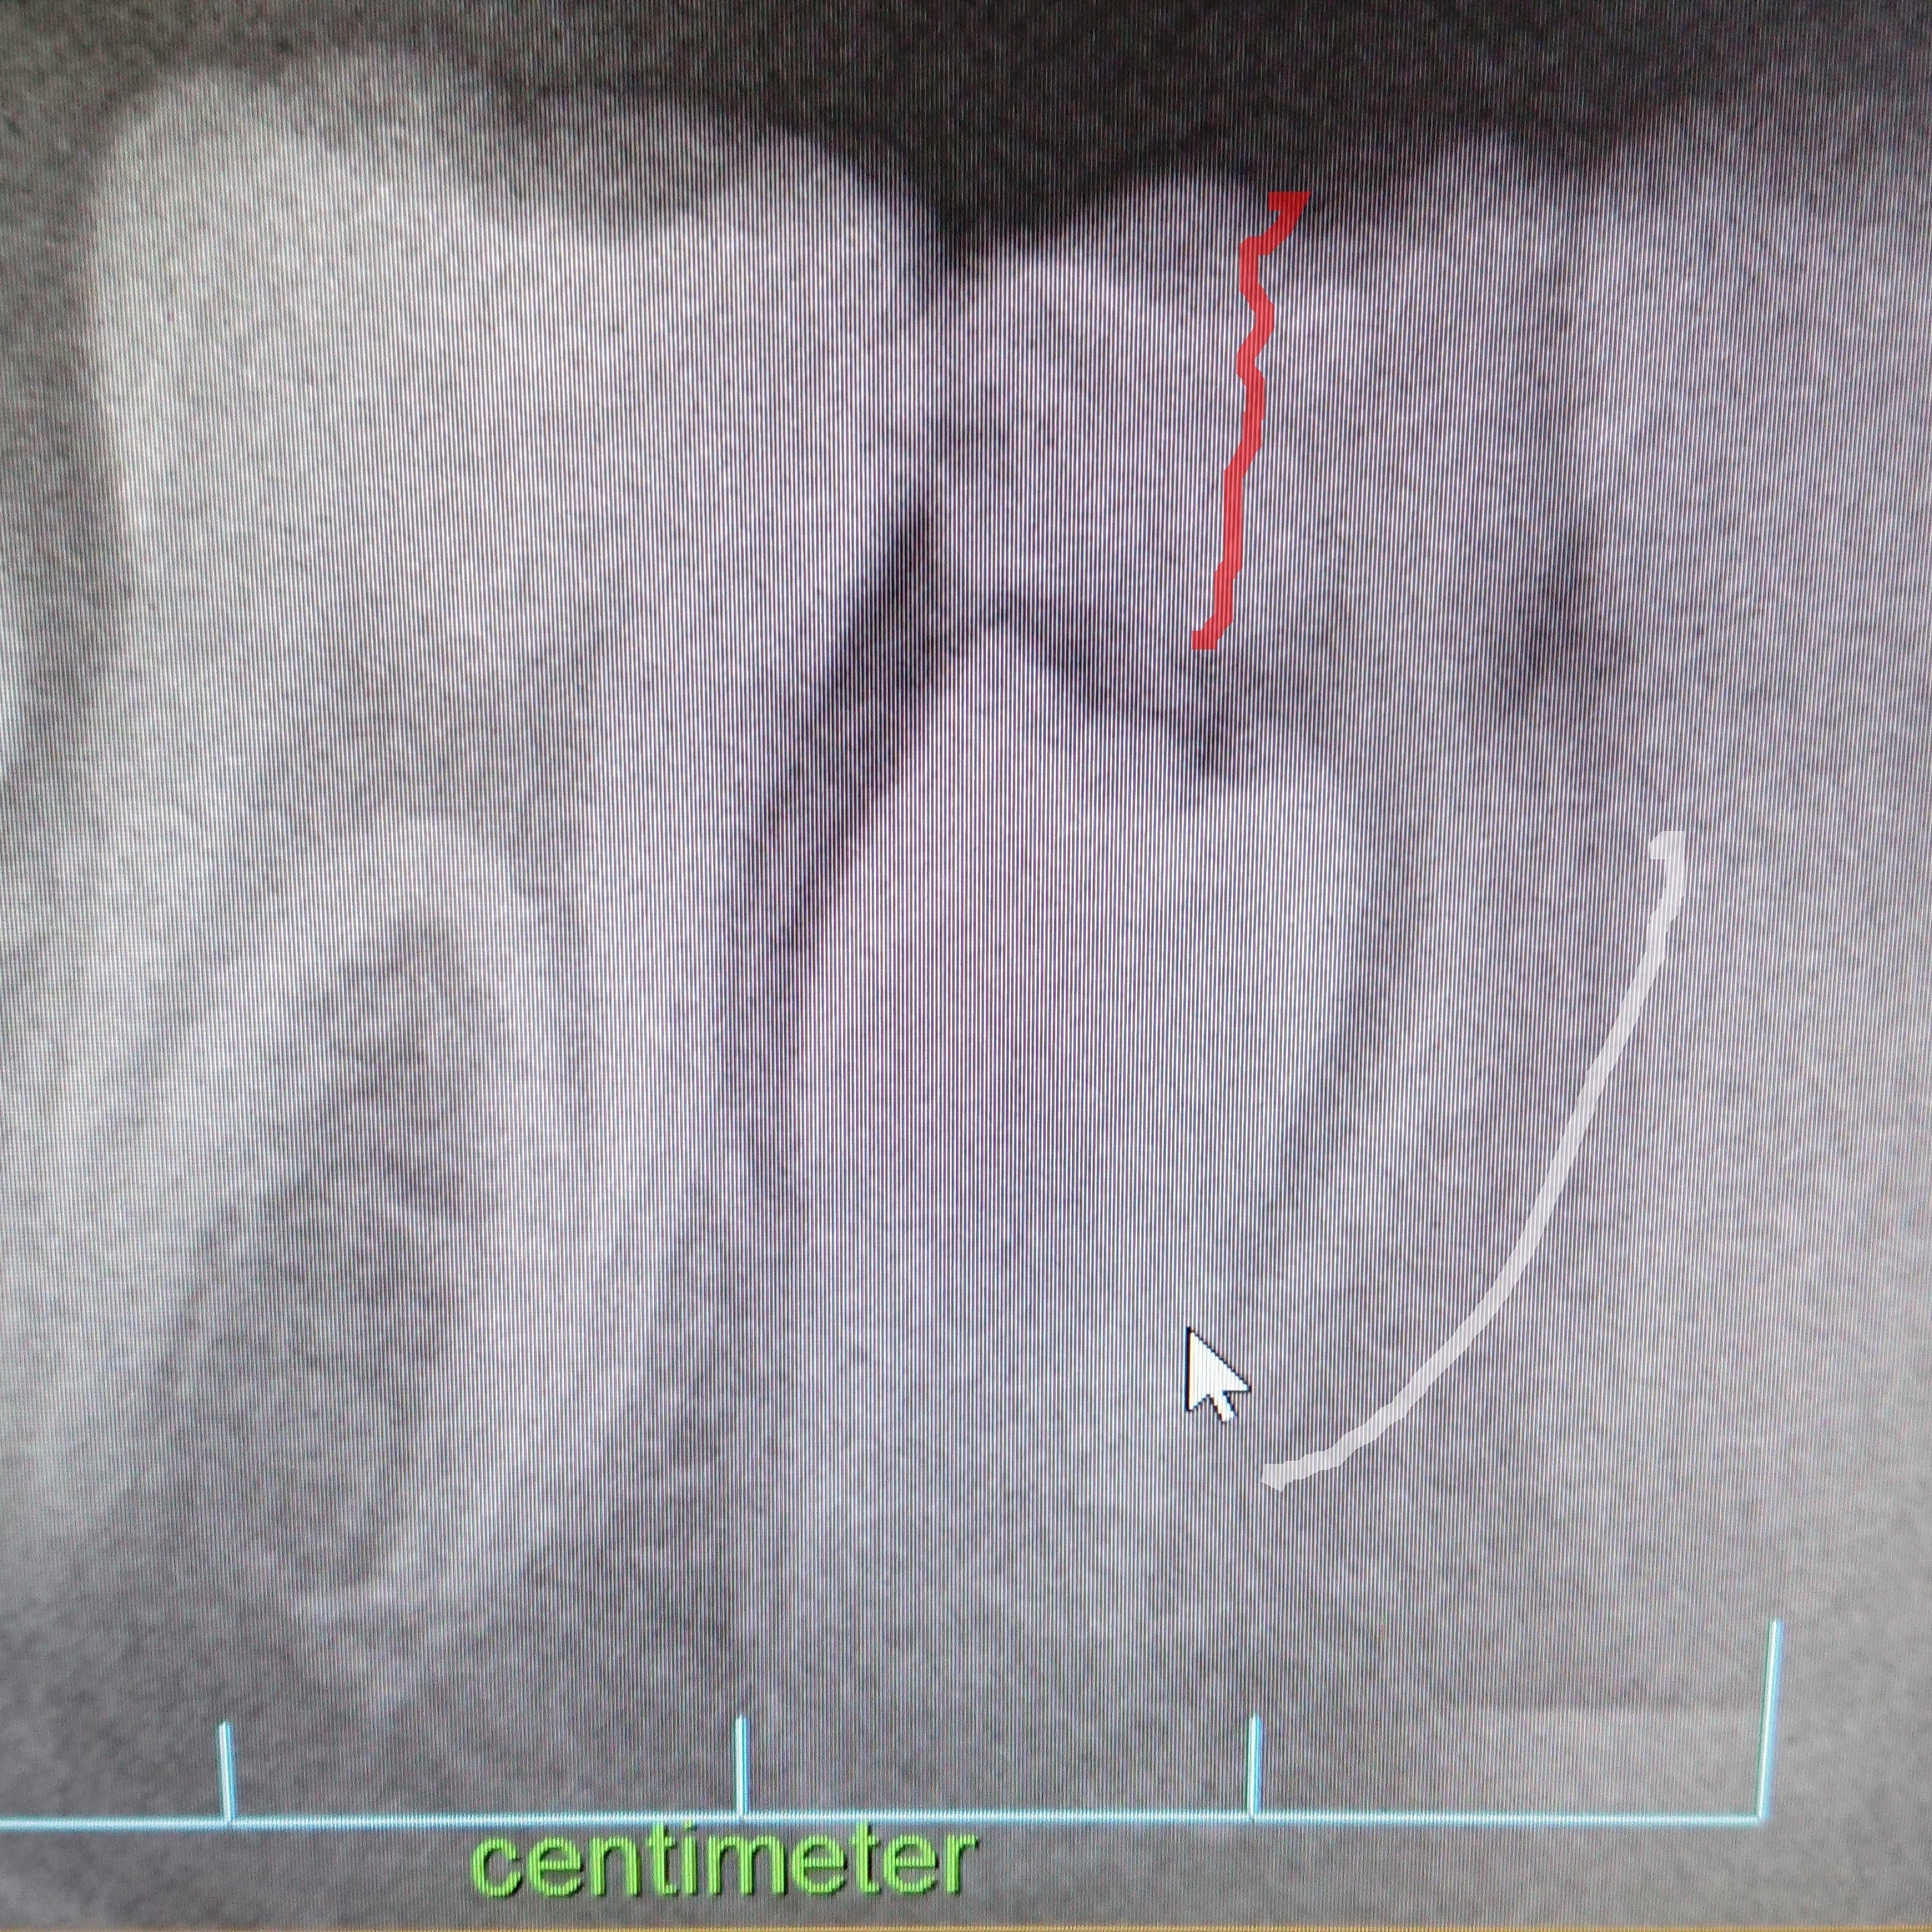

レントゲンを撮ったところ、この部分の乳歯の根はなく、また永久歯も特に今の段階では近いうちに生えそうにもないとの事です。 うちの子供は前方の歯(1,2番8本)が抜けるのも、生えるのも他のお子さんより早かったのですが、この 奥歯 は抜けるには早. 乳歯が抜ける時期は、乳歯と永久歯がいり乱れて存在しているため、大きさもバラバラです。 早い 時期に 歯の 永久歯の奥歯は、乳歯がもともと生えていない所(顔の真ん中から数えて6本目である6歳臼歯と呼ばれる第1大臼歯)から生えてきます。.